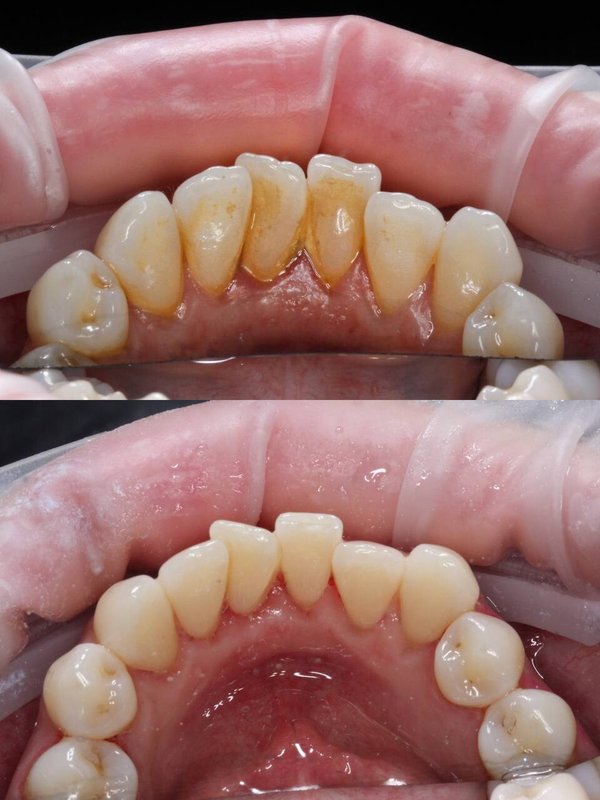

Фотогалерея